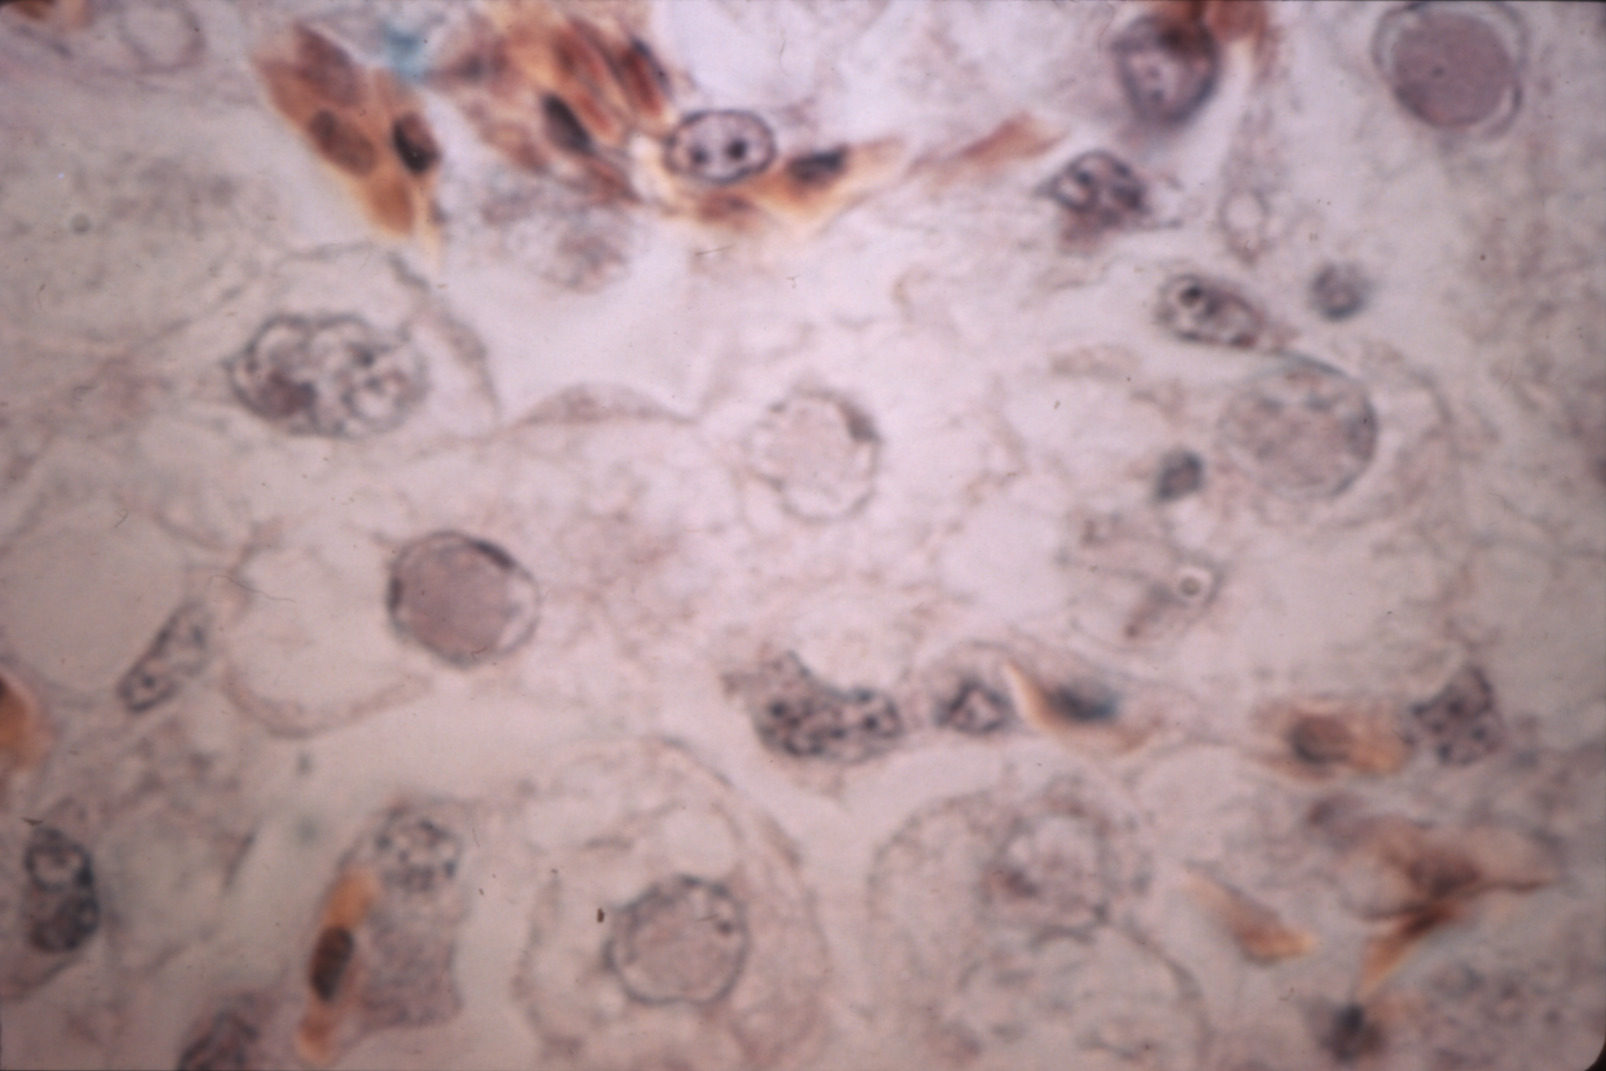

Inclusion body hepatitis of chickens (slide study set no. 2) Item Info

Inclusion body hepatitis of chickens (slide study set no. 2)

Slide Study Set #2, Inclusion Body Hepatitis, 2 sets (includes 44 color slides), 1973